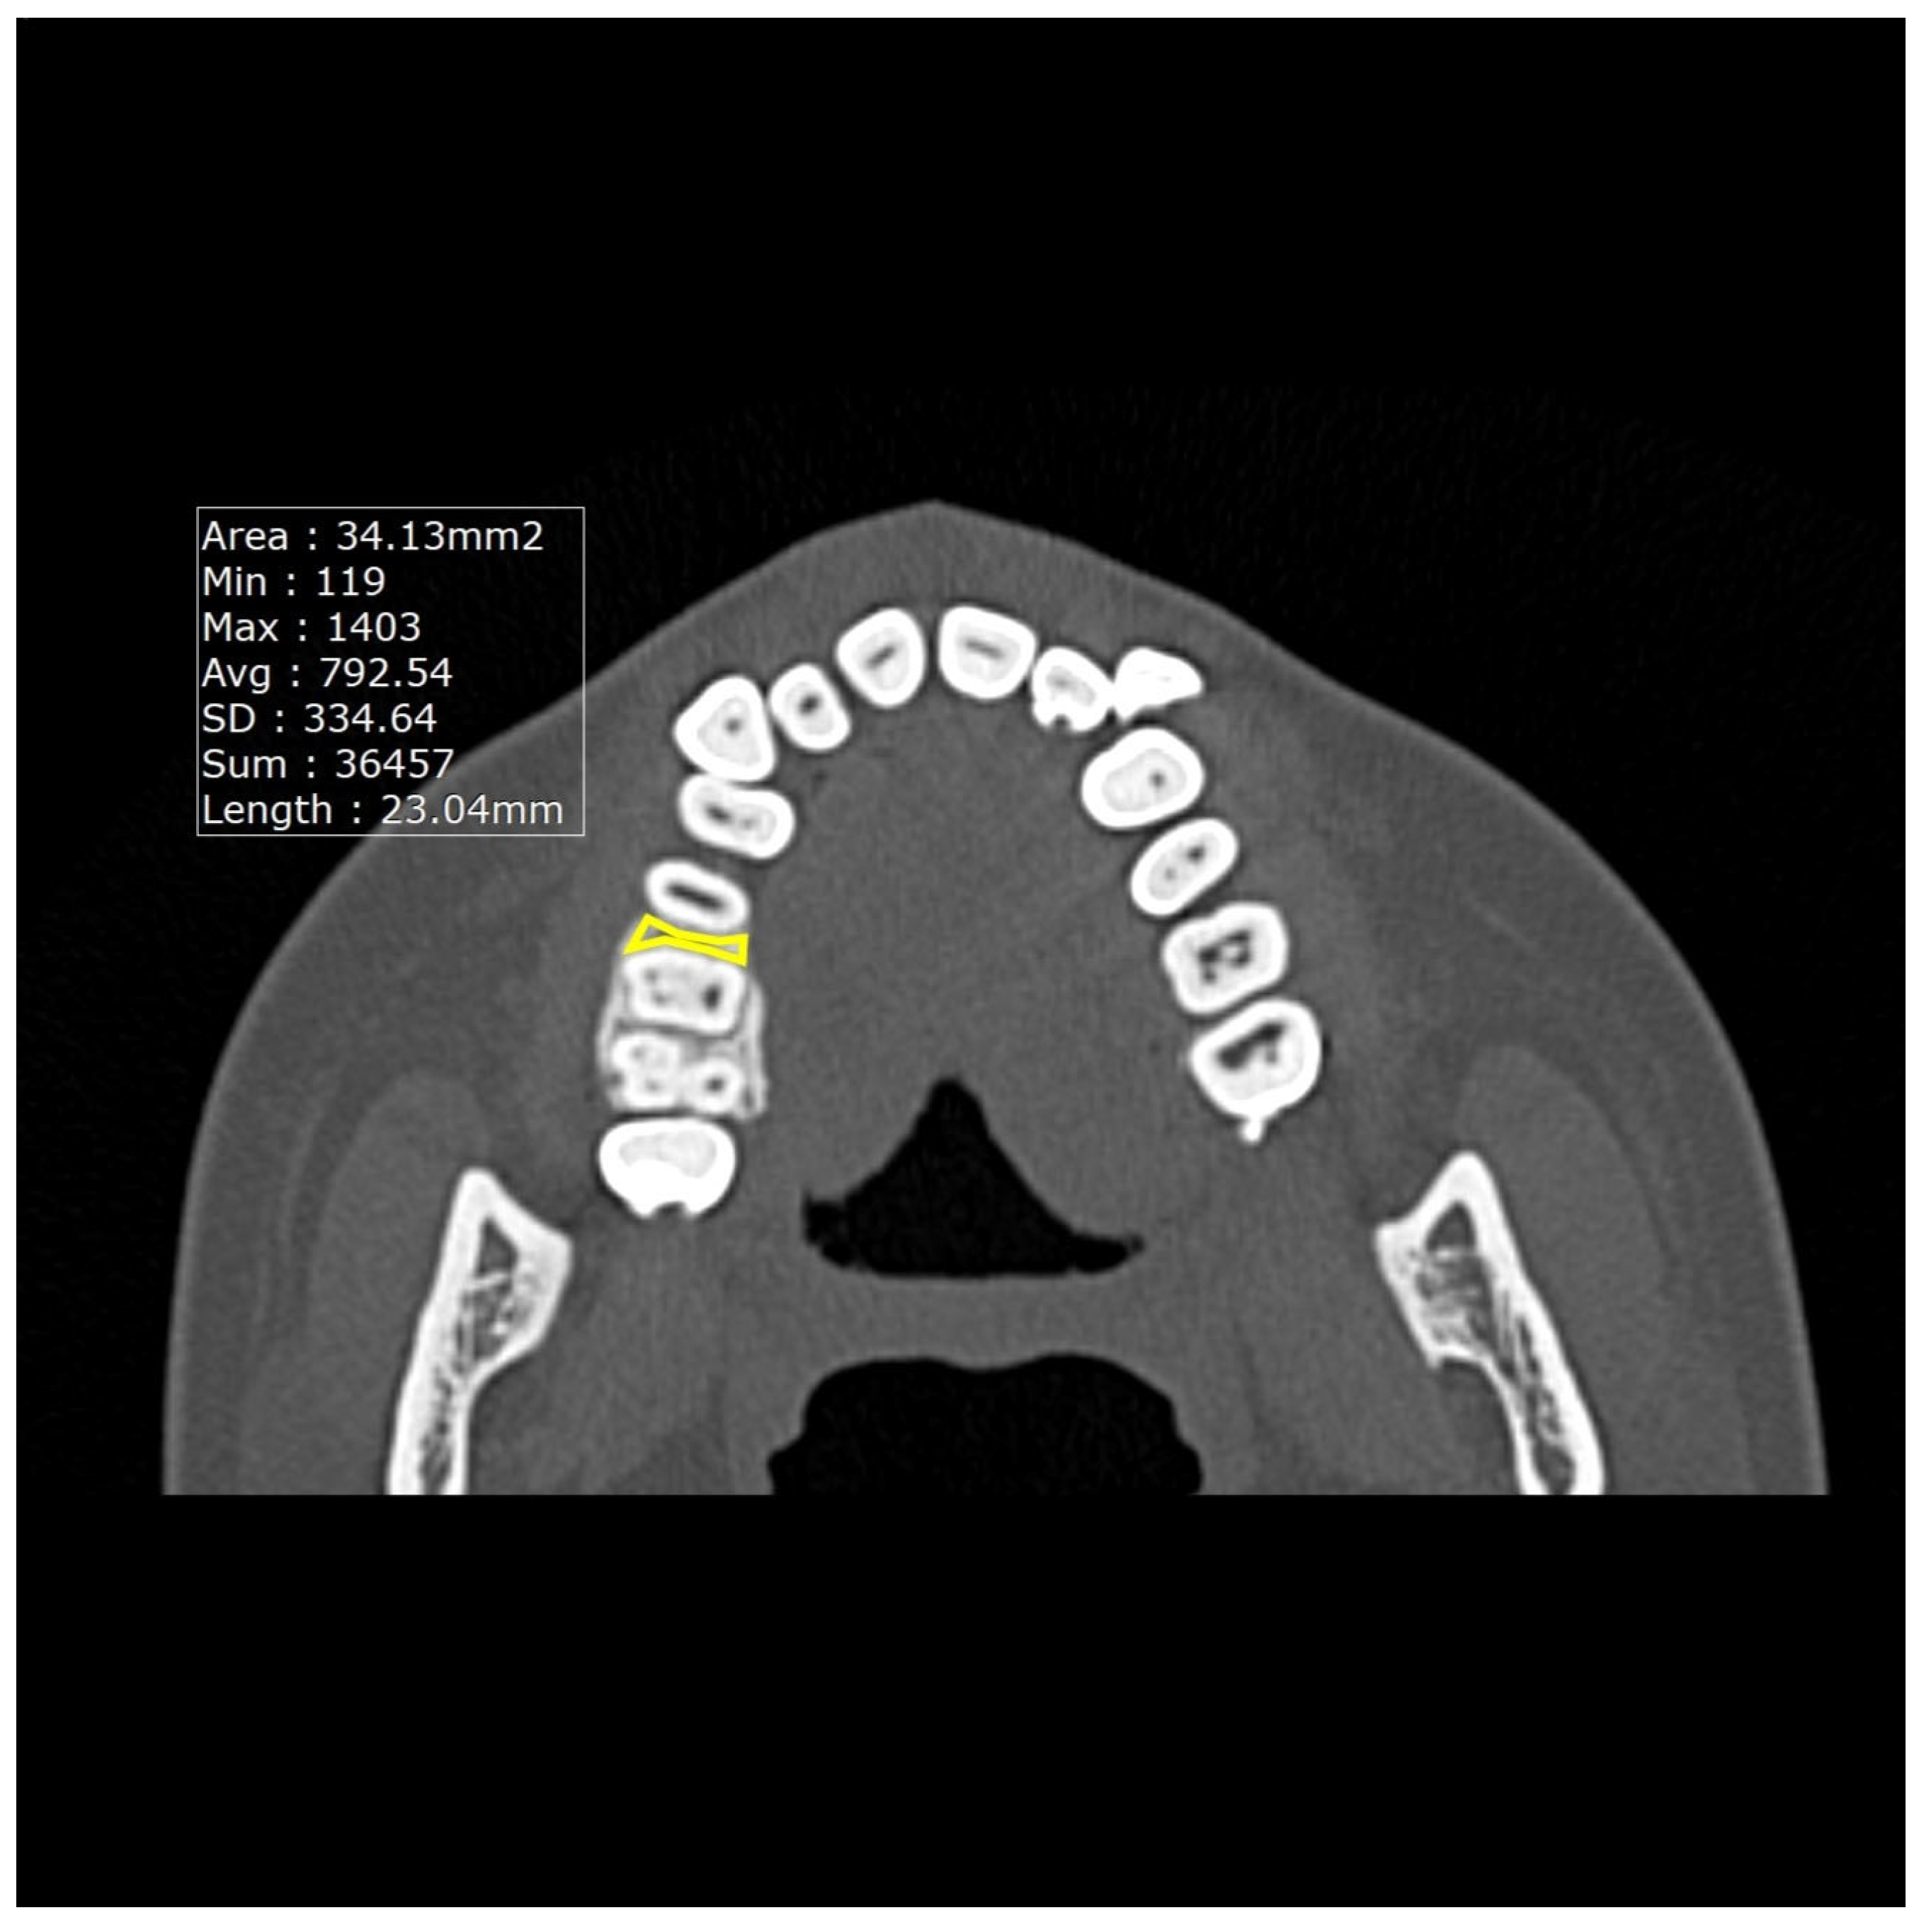

Measurements of the thickness of the alveolar crest cortical bone (Figure 1) were taken in the coronal plane from four sites: thickness between the maxillary canine and first premolar (Tmax3), thickness between the mandibular canine and first premolar (Tman3), thickness between the maxillary premolar and first molar (Tmax6), and thickness between the mandibular premolar and first molar (Tman6). Likewise, the densities of the CT values (Figure 2) between the maxillary canine and first premolar (Dmax3), the mandibular canine and first premolar (Dman3), the maxillary premolar and first molar (Dmax6), and the mandibular premolar and first molar (Dman6) were also obtained in the axial plane.

Figure 2.

Image showing the measurement of the average CT values in the maxilla.

The average CT values were measured using a CT workstation and software (INFINITT JAPAN, Tokyo, Japan). Previous studies have reported that the cortical bone width is the same on both sides [14], so some have measured it on one side only [10,11]. Therefore, in this study, only one side was measured. Cortical bone widths were measured three times, with the results comprising the average of the three measurements.